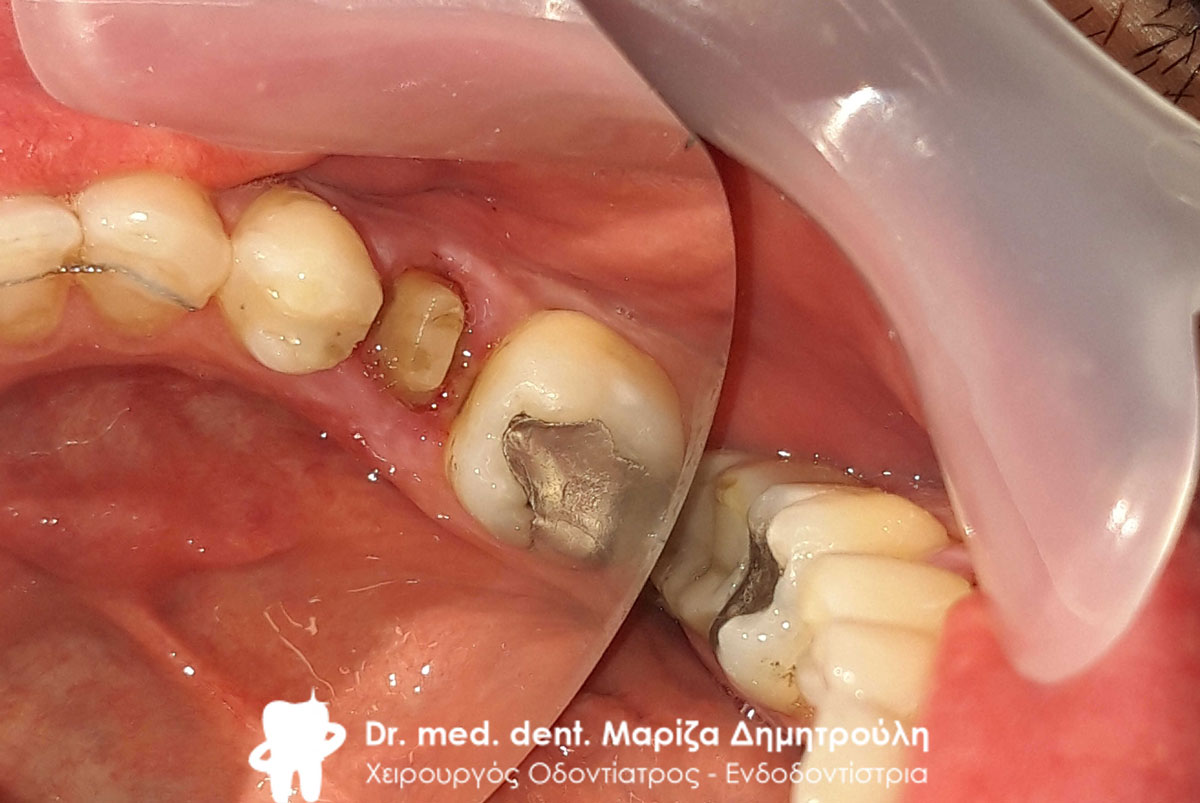

Περιστατικό – Ολοκεραμική στεφάνη / θήκη ζιρκονίου στην αριστερή πλευρά της κάτω γνάθου

Η ασθενής είχε ένα παλιό μαύρο σφράγισμα αμαλγάματος το οποίο την πονούσε. Μετά την κλινική και ακτινογραφική εξέταση του δοντιού αποφασίστηκε η αφαίρεση του παλιού σφραγίσματος, η νέα ανασύσταση και η κάλυψη του δοντιού με ολοκεραμική θήκη δοντιού, καθώς το οδοντικό έλλειμμα ήταν μεγάλο.

Αρχική κλινική εικόνα του δοντιού με το παλιό μαύρο σφράγισμα αμαλγάματος

Τελική εικόνα του δοντιού με τη νέα ολοκεραμική στεφάνη